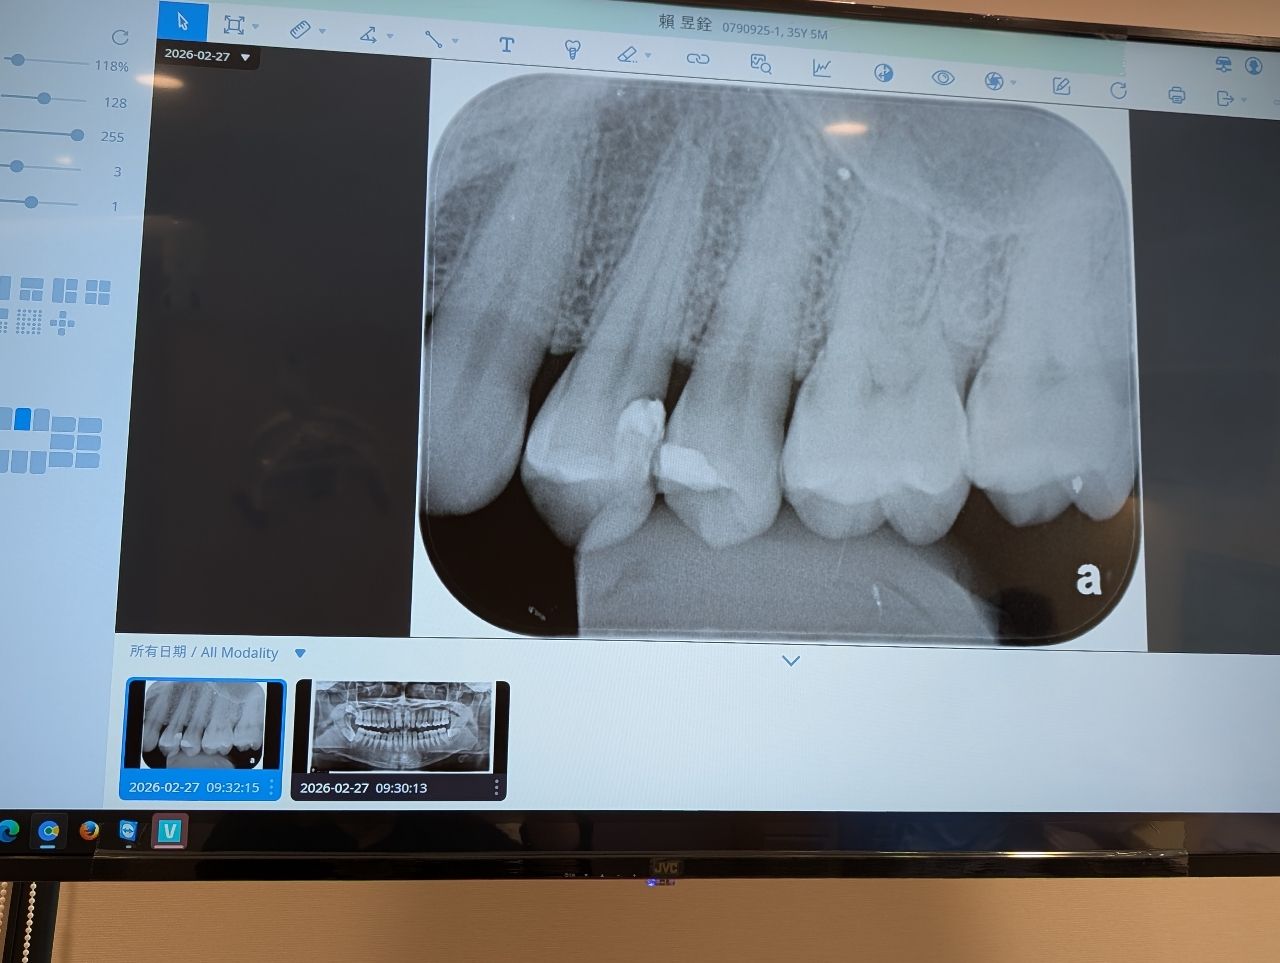

主角是左邊數過來第二顆牙齒

再來換去設備比較好的B診所,有幫忙拍X光片,醫生看完之後說那個補牙的洞很靠近神經

,可能有細菌跑進去感染導致咬硬物會痛,需要根管治療然後戴全瓷冠牙套,他看我猶豫

的樣子就先幫忙調整一下咬合說再觀察一個月

想請問各位大神這顆牙齒按照目前狀況有需要做根管治療嗎?